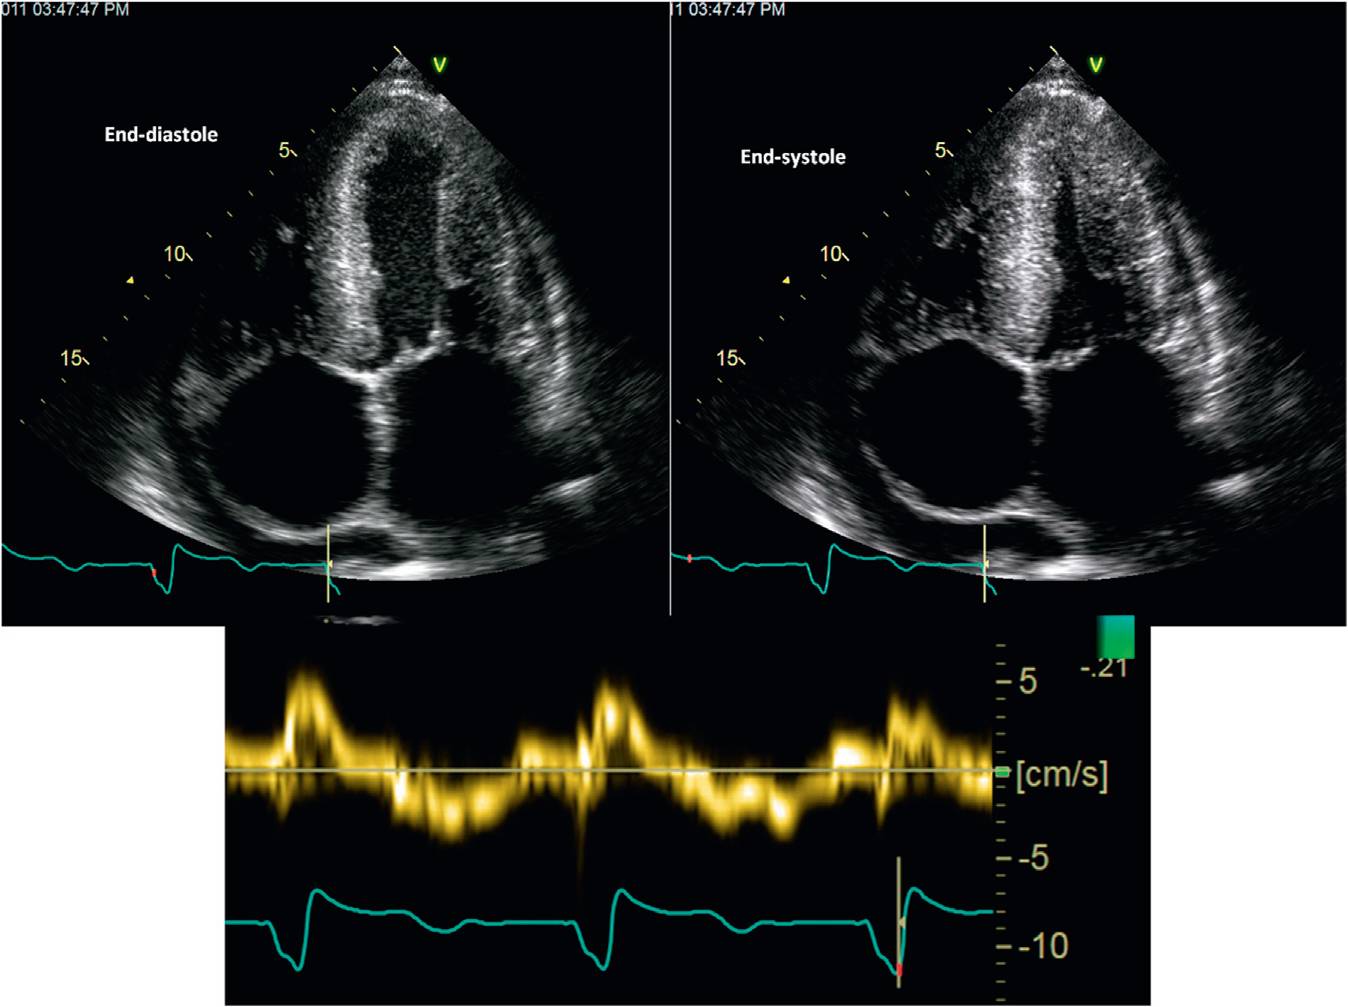

心脏淀粉样变 ECHO:LVH,室壁回声增强,可见颗粒状回声,二尖瓣主动脉瓣增厚,少量心包积液。

心脏淀粉样变 ECHO:LVH,室壁回声增强,可见颗粒状回声, 心包积液。

CA左室整体收缩期纵向峰值应变,基部收缩受损,心尖部接近正常(apical sparing)